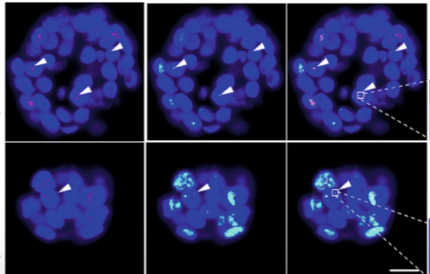

Entschlüsselung der Mechanismen der Immortalisierung mit Hilfe von Tumororganoiden

p-care Partner Stefan Schoeftner und sein Team an der Universität Trieste veröffentlichen einen wissenschaftlichen Artikel, in dem die Verwendung von Tumororganoiden Einblicke in die Mechanismen der Immortalisierung von Krebszellen gibt (Nature Communications)